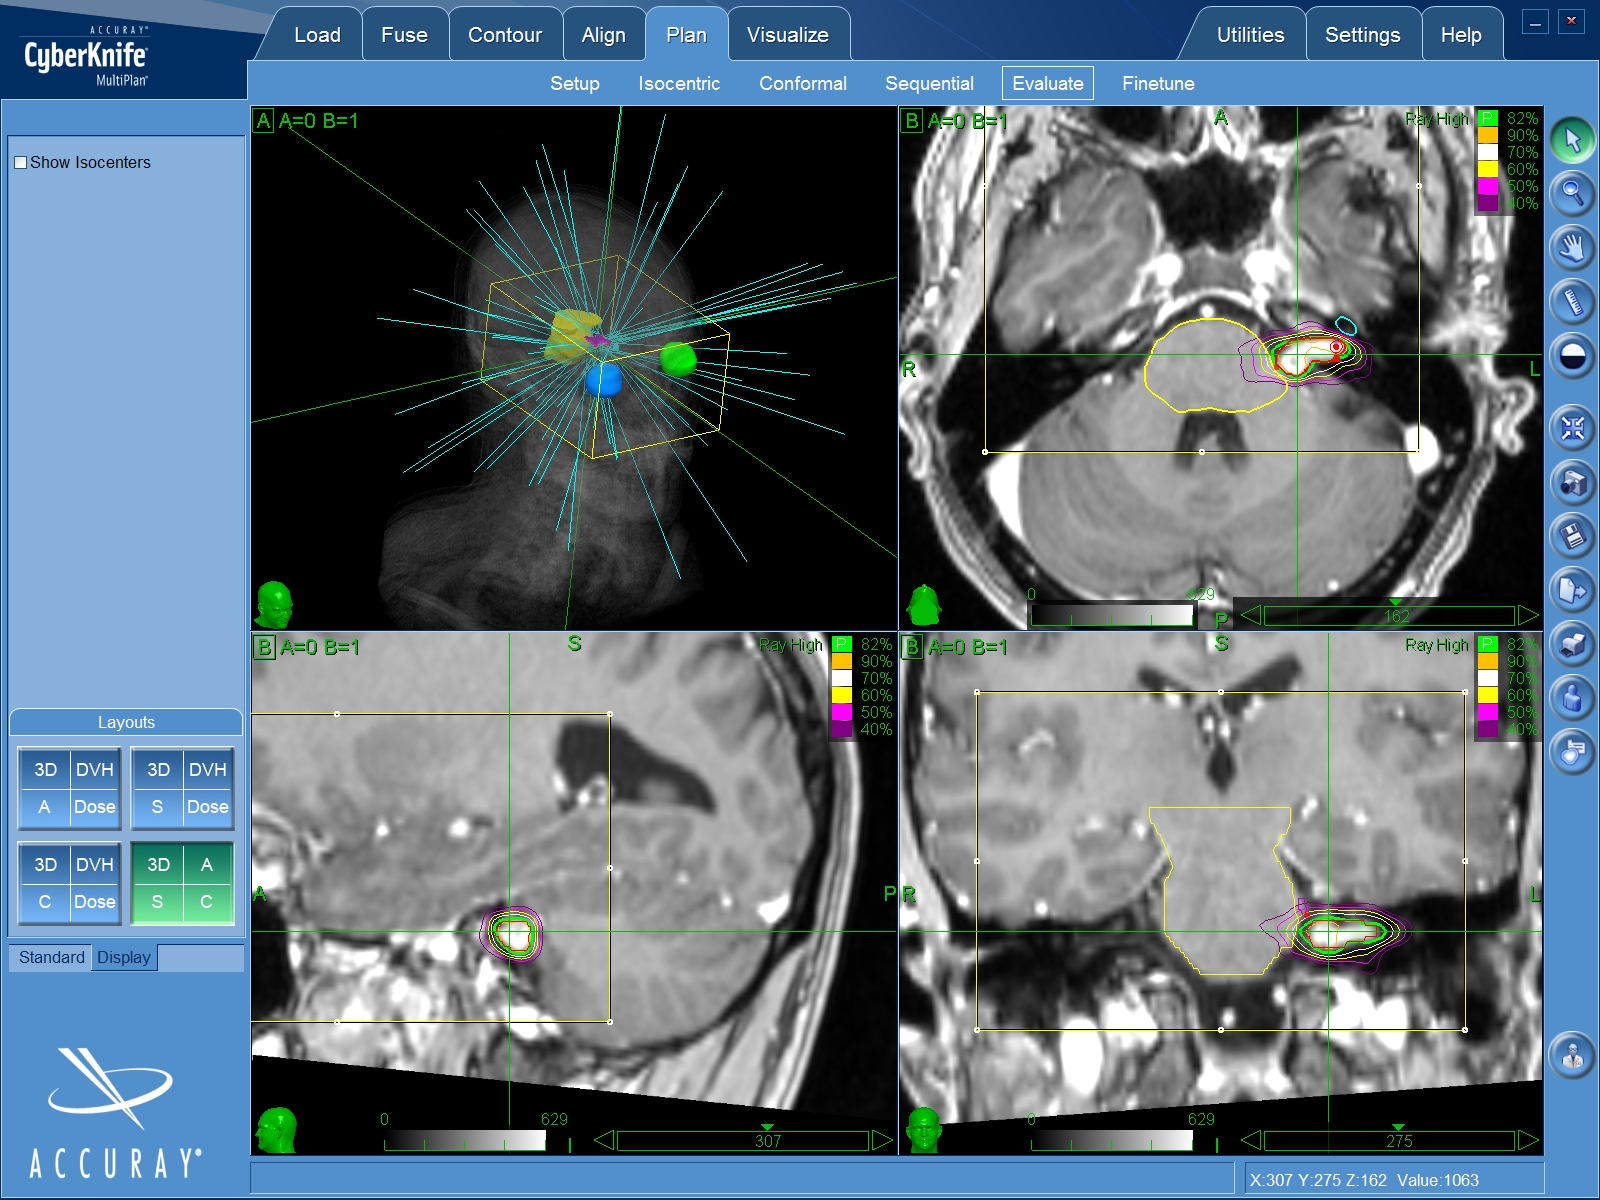

Stereotaktische Bestrahlung

Aufgrund des gutartigen und langsamen Wachstums der Akustikusneurinome ist eine konventionelle Bestrahlung nicht effektiv. Hier ist eine hochdosierte Präzisionsbestrahlung, wie zum Beispiel die Gamma Knife- oder CyberKnife-Bestrahlung (Radiochirurgie), notwendig. Ziel dieser Hochpräzisionsbestrahlung ist der Stopp des Wachstums des Tumors. Oft kann der Tumor mit dieser Methode sogar etwas verkleinert werden. Wie bei der konventionellen Bestrahlung müssen die umliegenden neuronalen Strukturen (welche die Nervenzellen betreffen) jedoch außerhalb des Bestrahlungsfeldes liegen, was durch eine millimetergenaue Planung gewährleistet ist.

Trotzdem ist eine effektive Bestrahlung der Tumorränder schwierig. Insbesondere bei großen Tumoren und bei direkter Nachbarschaft zum Hirnstamm ist eine solche Bestrahlung nicht möglich. Bei Rezidiven ist eine erneute Strahlentherapie meist nur eingeschränkt möglich. Eine operative Therapie ist bei vorbestrahlten Tumoren aufgrund der Vernarbung des Gewebes außerordentlich schwierig. Die radiochirurgische Behandlung führt Prof. Feigl bei seinen PatientInnen im Cyberknife-Zentrum Südwest in Göppingen durch. Nähere Informationen hierzu finden Sie unter https://www.radiochirurgicum.de/cyberknife-expertenteam.php.

Die Radiochirurgie mit dem Gamma- oder Cyberknife ist eine besondere Form der Strahlentherapie, die technisch sehr aufwändig ist, da es sich um eine Hochpräzisionsbestrahlungsmethode handelt. Viele Strahlen aus unterschiedlichen Richtungen überkreuzen sich dabei genau im Zielbereich, dem Tumor, der zuvor mit entsprechenden hochauflösenden MRT- und CCT-Bildern exakt lokalisiert wurde. Im Tumorbereich kann so eine sehr hohe Strahlendosis erreicht werden, während die noch ungebündelten einzelnen Strahlen das gesunde umliegende Gewebe schonen. Da die hohe Strahlendosis nur dort entsteht, wo sich die Strahlen kreuzen, kann der Tumor mit einer Präzision im Submillimeterbereich bestrahlt werden. Bei radiochirurgischen Behandlungen wird daher keine allgemeine Narkose benötigt.

MRT-Bildgebung

Der im Planungs-MRT-Bild eingezeichnete Tumor wird aus vielen verschiedenen Richtungen mit niedriger Dosis bestrahlt. So wird nur im Bereich des Tumors die benötigte hohe Strahlendosis erreicht und das umliegende Gewebe geschont.